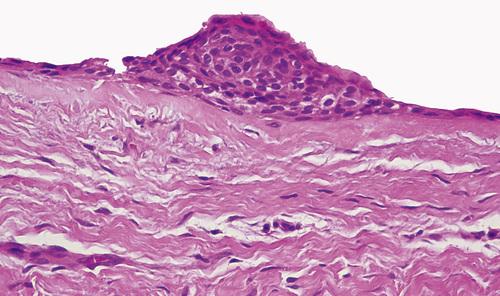

Histopathologic Features

- loosely arranged fibrous connective tissue wall

- islands or cords of odontogenic epithelial rests

- two to four layers of flattened nonkeratinizing cells

- focal areas of mucous cells in epithelial lining

This noninflamed cyst shows a thin, nonkeratinized epithelial lining and a loosely arranged fibrous connective tissue wall.

dentigerous cyst, noninflamed

This inflamed cyst shows a thick epithelial lining with hyperplastic rete ridges and diffuse chronic inflammatory infiltrate.

dentigerous cyst, inflammed